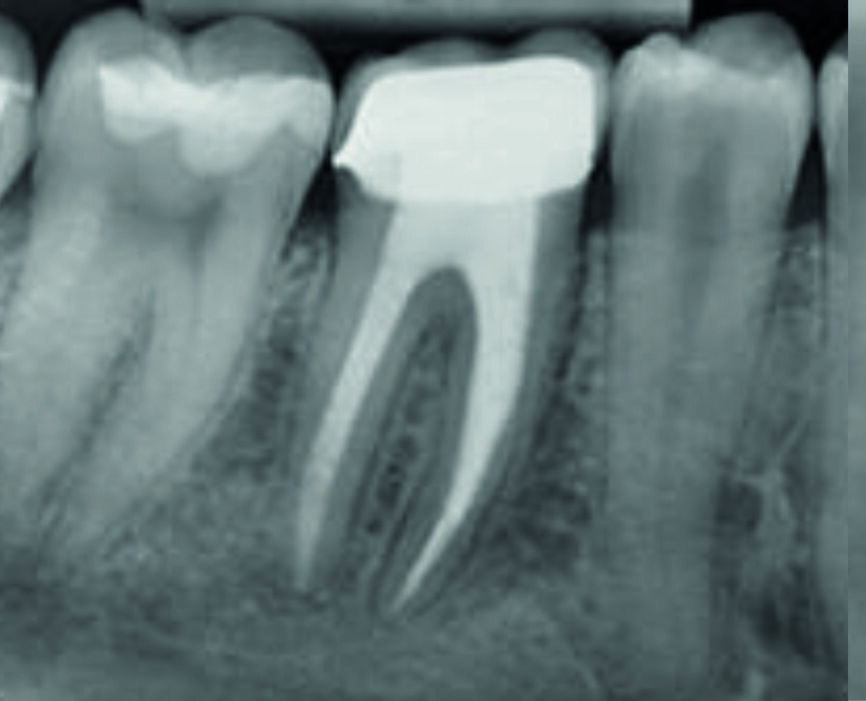

The calcium hydroxide paste was removed ten days later. The complete removal of paste from the root canal walls was accomplished by passive ultrasonic irrigation and 10% citric acid, using an endodontic tip (ESI, EMS) for more precise cleaning. Taking into consideration the extent of the apical root resorption, it was decided to perform orthograde MTA obturation of the distal canal space to arrest the resorption. The material was placed into the canals with the MAP System carrier (Produits Dentaires; Fig. 3) by the means of a 5 mm apical plug and was condensed vertically with a hand plugger. After radiographic examination of the accuracy of the apical plug (Fig. 4) and a setting period, the entire canal and the mesial canals were obturated with TotalFill BC (FKG Dentaire; Fig. 5). The orifices were adhesively sealed and the tooth was definitively restored with light-curing composite and prepared for a crown.

Fig. 4: Obturation of mesial canals and a 5 mm apical plug of MTA distally

Fig. 5: Control radiograph after final obturation